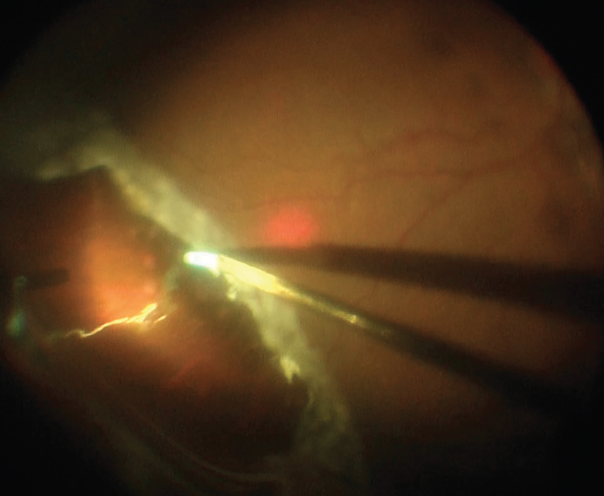

<p>Figure 1. This patient had a superotemporal GRT with a macula-off detachment.</p>

Figure 1. This patient had a superotemporal GRT with a macula-off detachment.

The posterior segment examination showed posterior vitreous separation and a macula-off rhegmatogenous retinal detachment (Figure 1). The tear extended from approximately 12:30 o’clock to 4:00 o’clock.